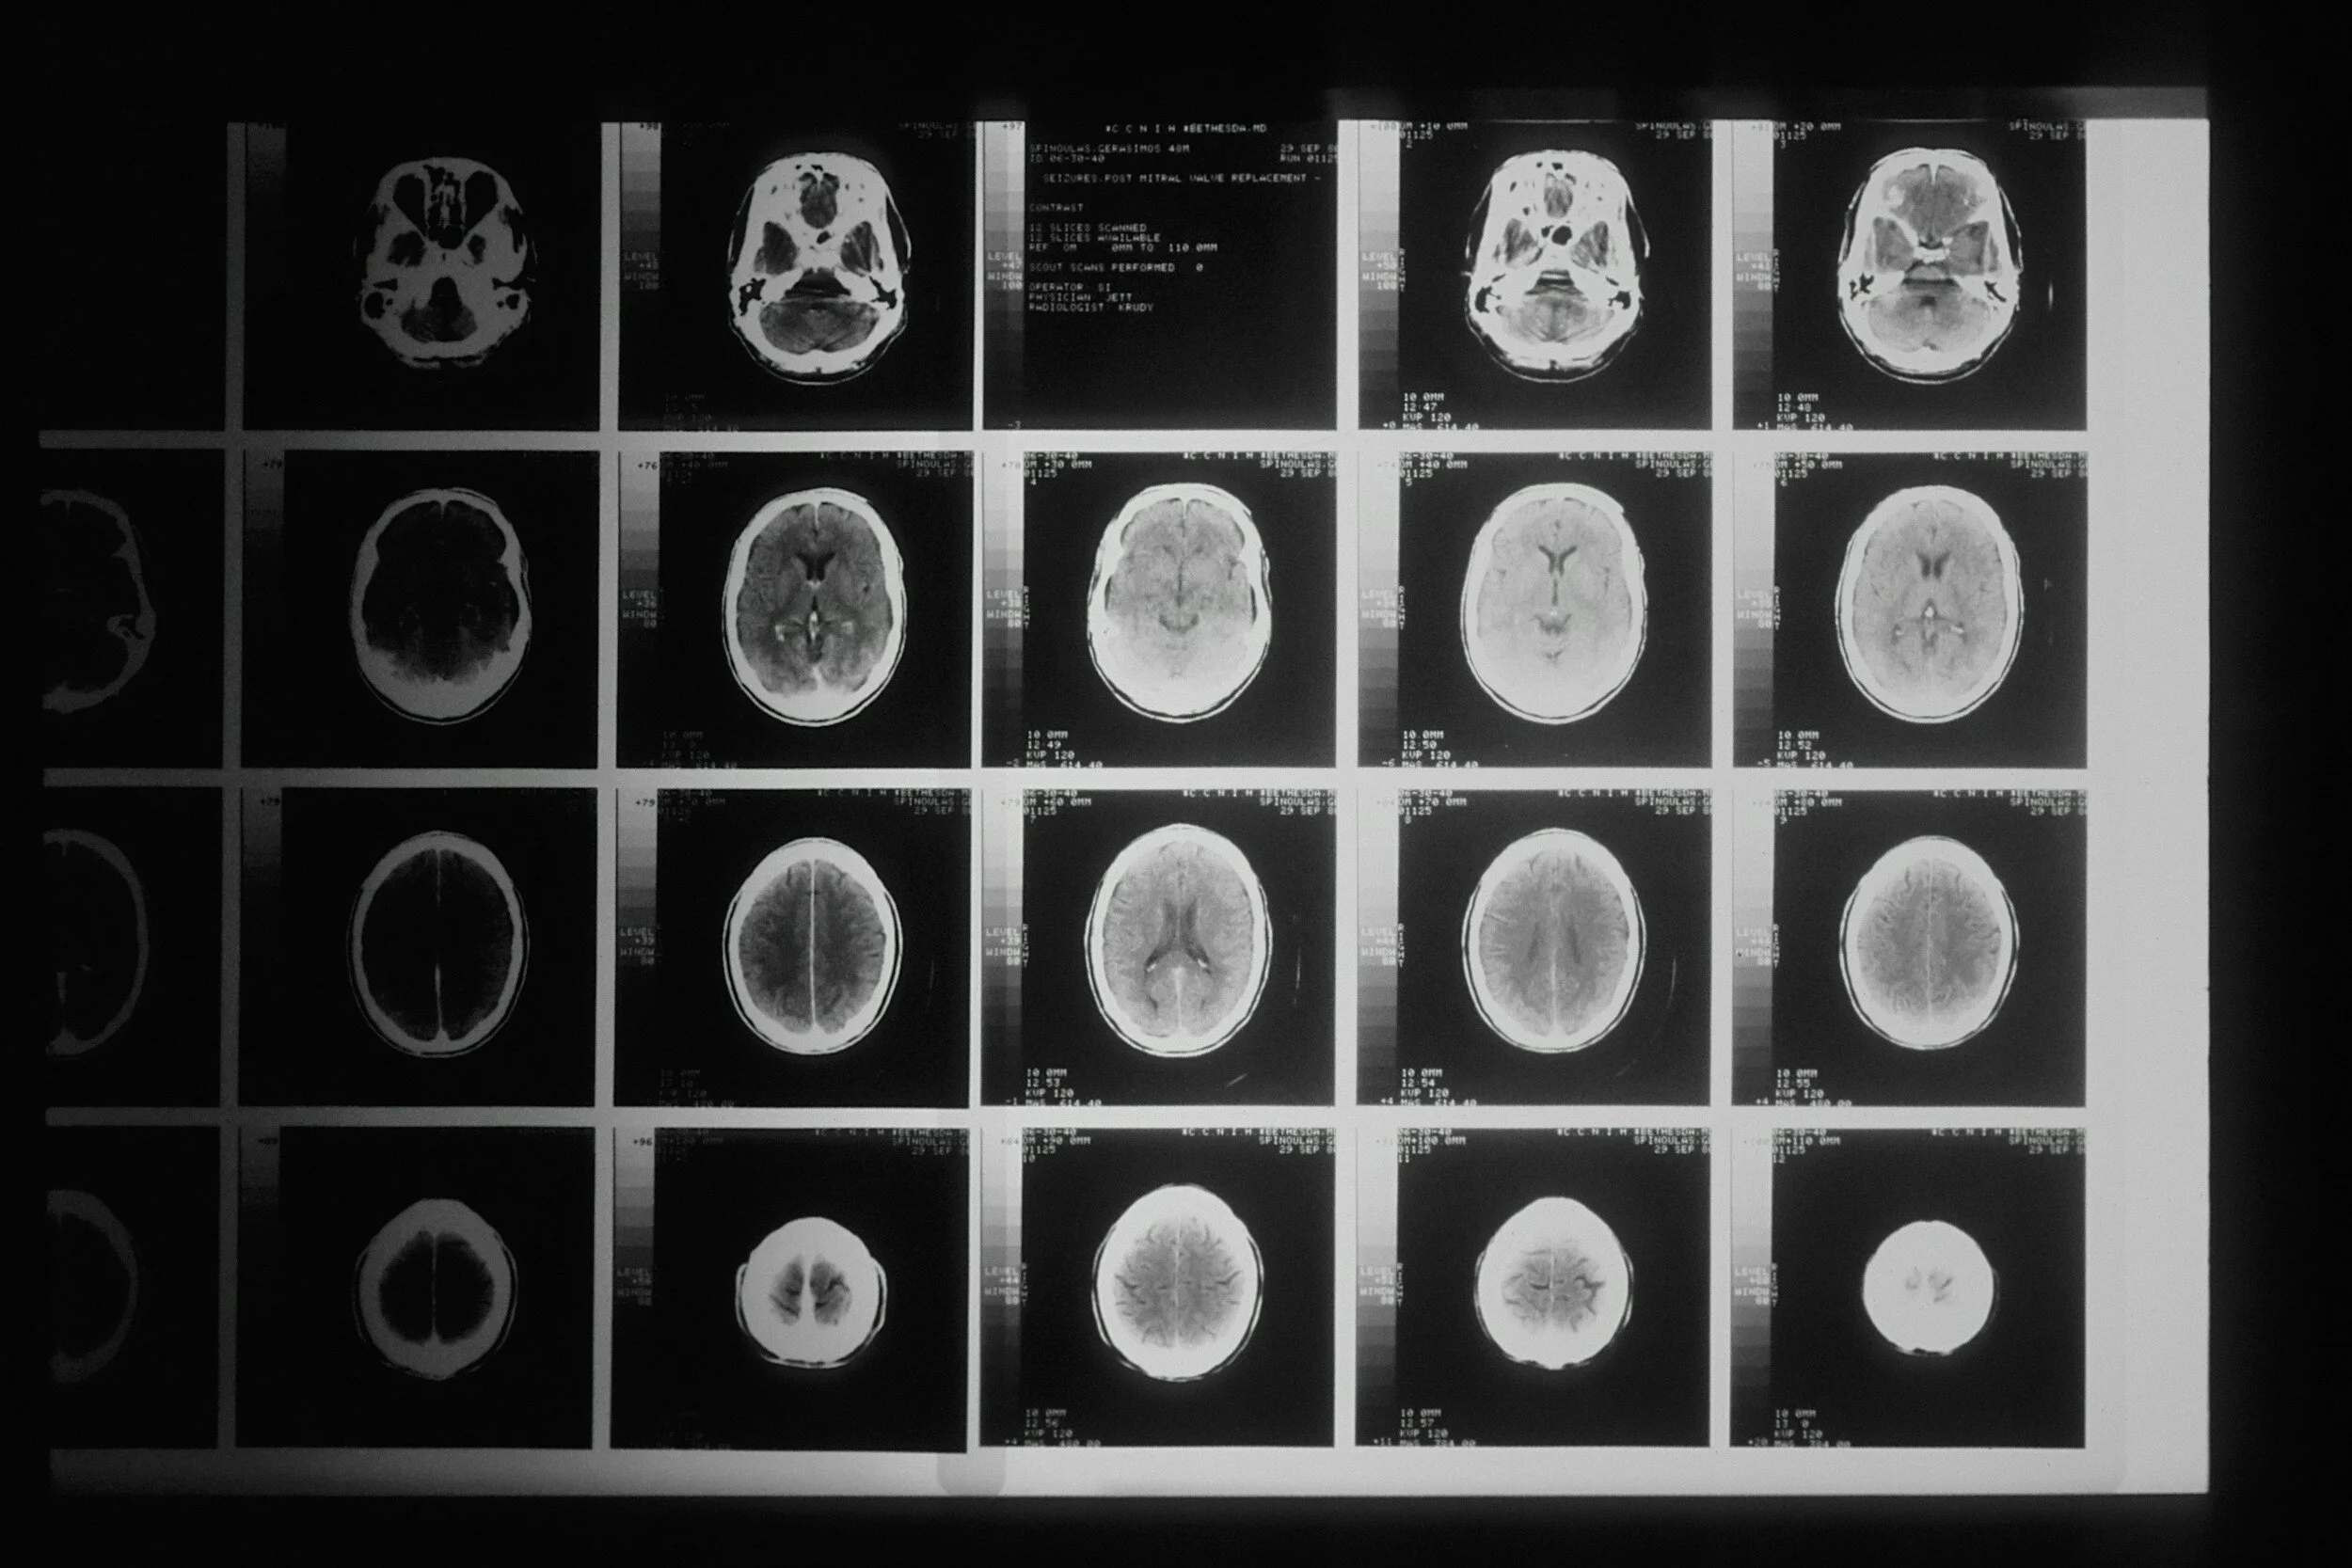

A young lady who loves horses fell off her horse for the third time and began to have seizures shortly after.  Rushed to the hospital, she had a normal CT scan of her head, but an electroencephalogram (EEG) showed she had post-concussive syndrome.

The primary concern for this young lady is the abnormal EEG. Traumatic brain injury is the result of repetitive head impacts, and she had fallen off her horse for the third time.  Some young people suffer brain injuries because of traffic accidents, sports like football and soccer, and falls for a variety of reasons. But TBI is not just relegated to young people and can occur in older individuals as well.

Analysis of brains from athletes and military personnel who have experienced TBI shows shrinkage of parts of the brain during neurobiological exams (from autopsy on dead individuals). A portion of the brain is the blood-brain barrier, a network of blood vessels and tissue comprised of closely spaced cells.  It is delicate and keeps harmful substances from reaching the brain. This barrier is breached in TBI, especially CTE.  The blood brain barrier is critical as a filter and it can be breached in many illnesses, but most prominently in TBI.

Doctors are addressing this now.  New helmets are designed to protect the head in all sports, but even that is controversial.  You can wear a special protective helmet, but if the head hits a hard object many times (like a hard surface), the brain moves back and forth, and there are likely to be microscopic hemorrhages and various degrees of damage to the blood-brain barrier (mentioned above).  Our lady’s seizure activity was most likely because of an injury to her blood-brain wall.